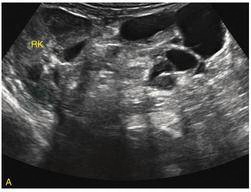

成熟型腹膜后畸胎瘤声像表现为囊实混合性肿块,边界清晰,可有脂液分层及钙化强回声团伴后方声影(图3)。超声显示含有脂肪和钙化的团块,提示畸胎瘤。巨大腹膜后畸胎瘤可压迫肾脏、输尿管,引起尿路梗阻,或使腹主动脉、下腔静脉位移。

图3 腹膜后畸胎瘤

A.右肾受压,肾盂轻度扩张;B.团块内有钙化强回声(箭头)